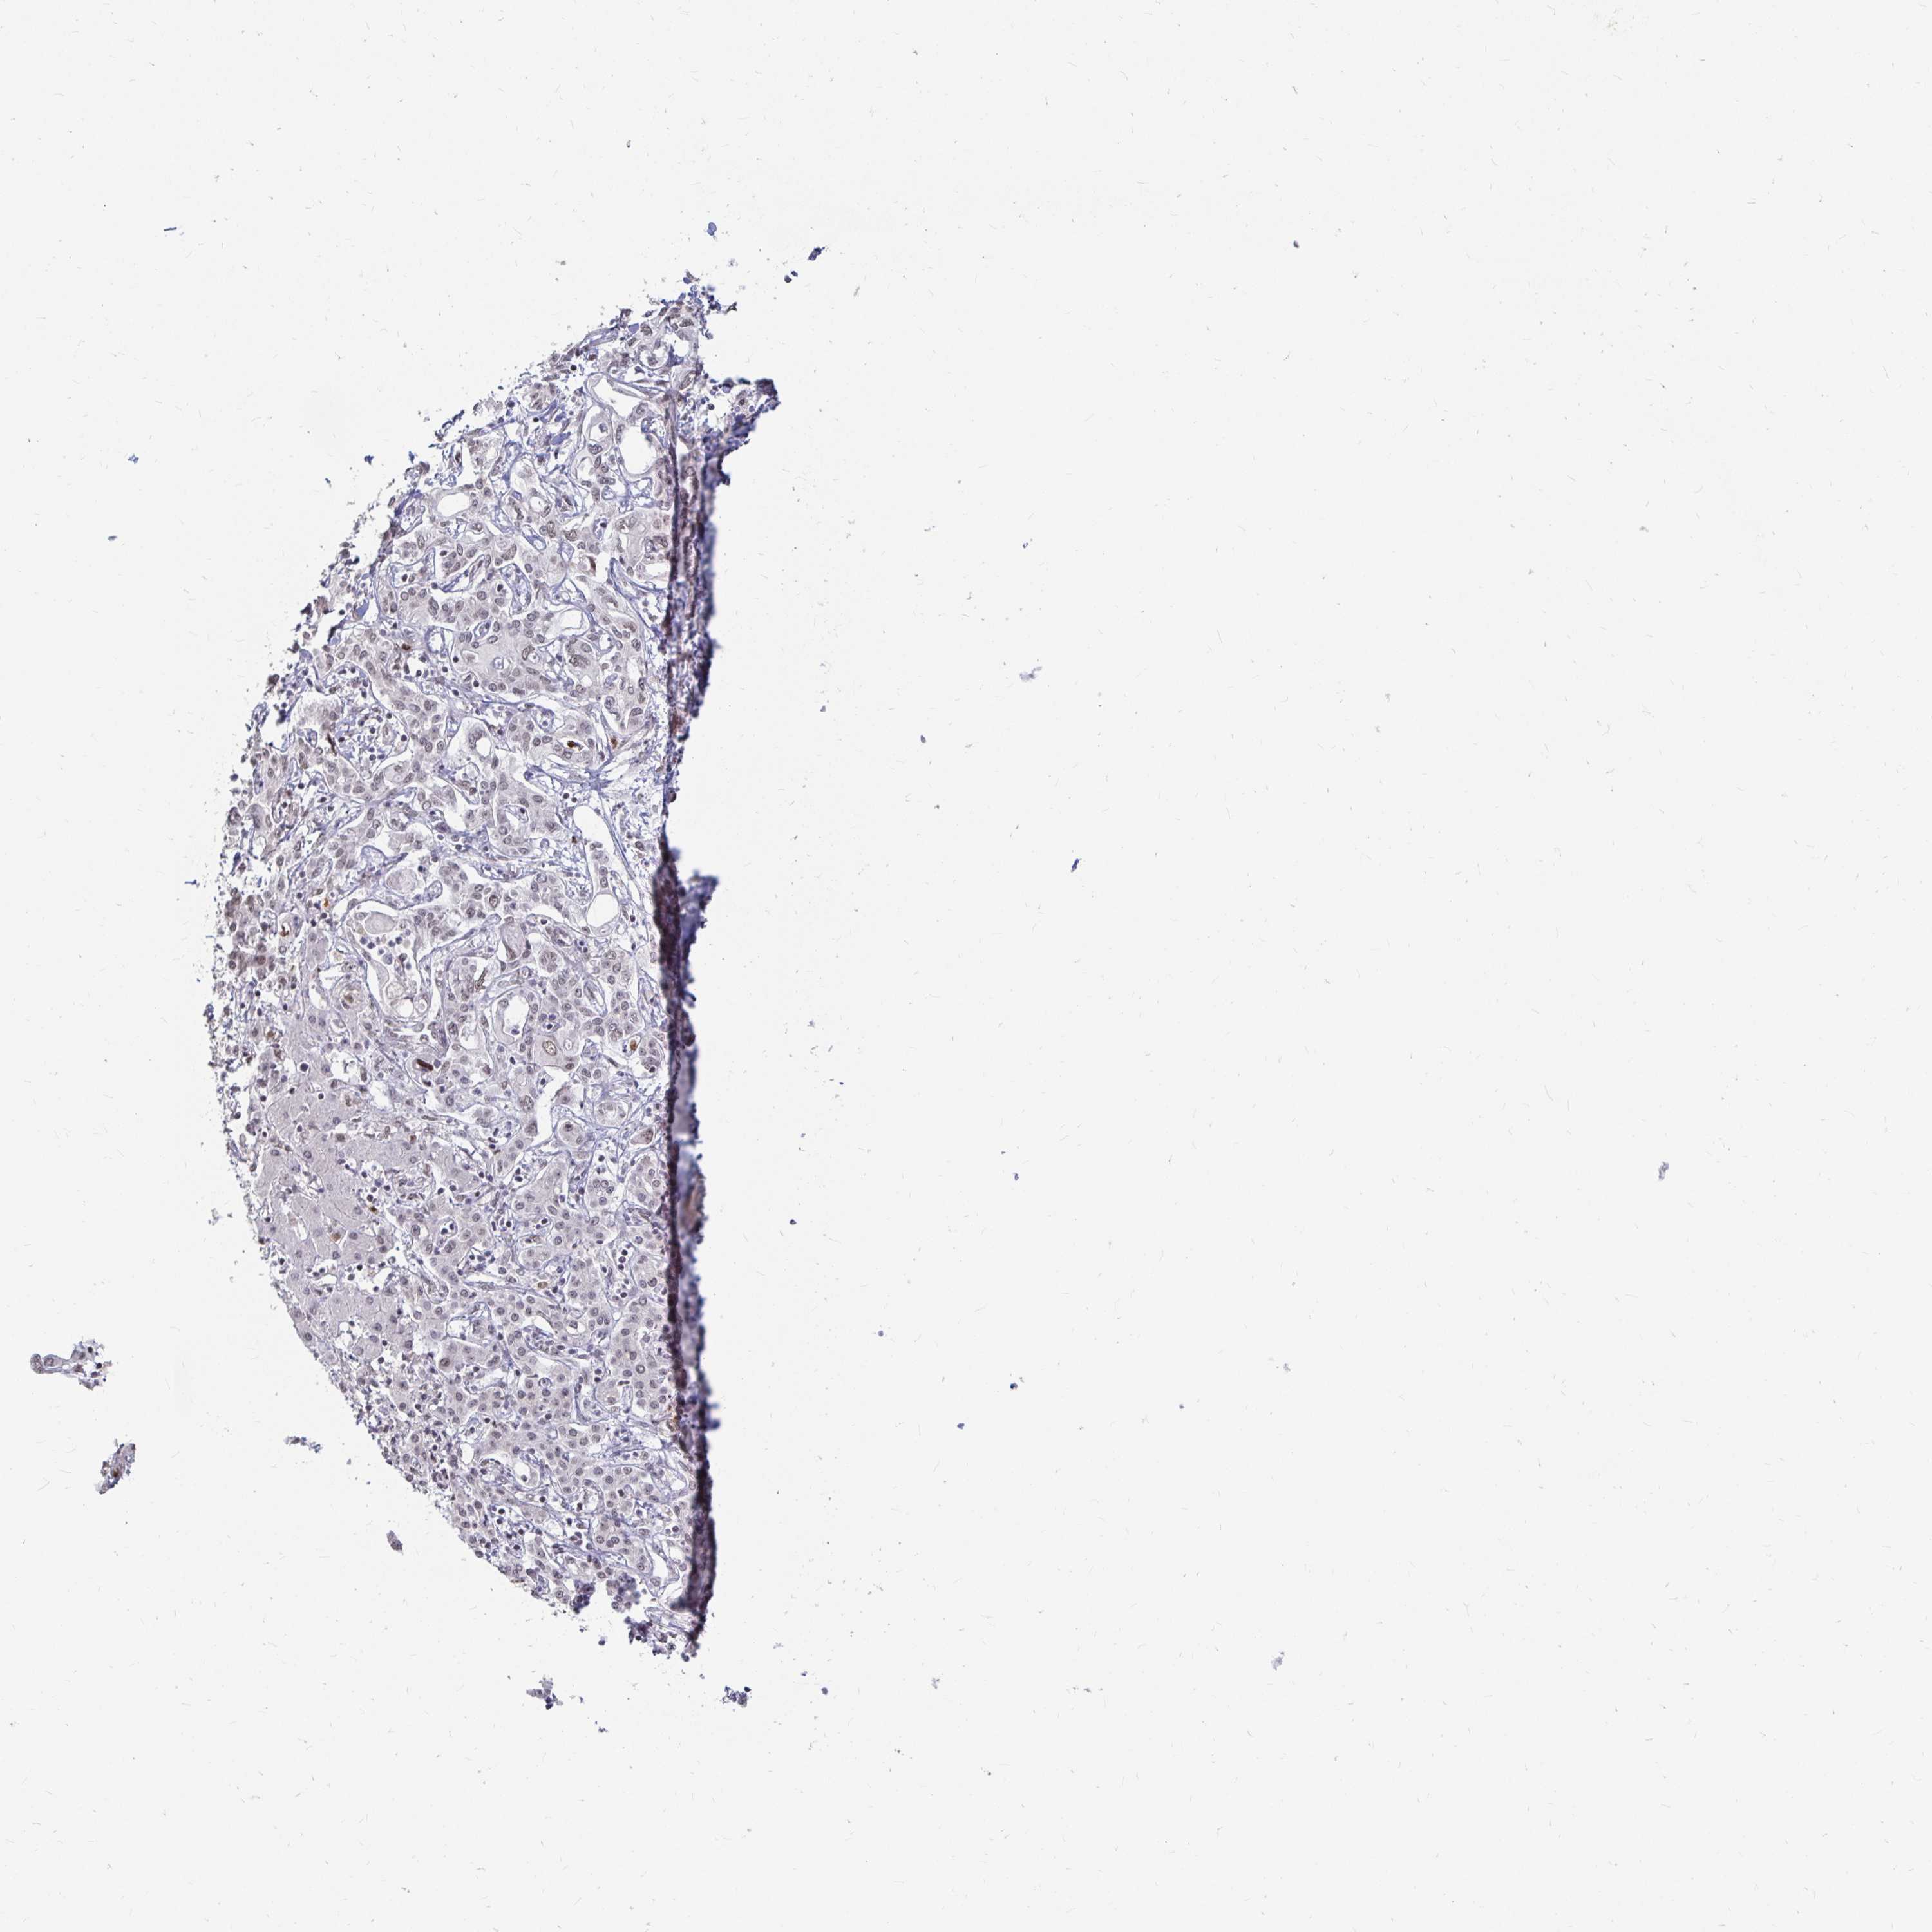

LIVER CANCER - Protein expressioni

A mouse-over function shows sample information and annotation data. Click on an image to view it in a full screen mode. Samples can be filtered based on level of antibody staining by selecting one or several of the following categories: high, medium, low and not detected. The assay and annotation is described here.

Antibody stainingi

Antibody staining in the annotated cell types in the current human tissue is reported as not detected, low, medium, or high, based on conventional immunohistochemistry profiling in selected tissues. This score is based on the combination of the staining intensity and fraction of stained cells.

Each image is clickable and will lead to virtual microscopy that enables deeper exploration of all samples and also displays staining intensity scores, fraction scores and subcellular localization as well as patient and tissue information for each sample.

Antibody HPA041057

Antibody HPA058707

Antibody CAB011532

Staining

High

Medium

Low

Not detected

Intensity

Strong

Moderate

Weak

Negative

Quantity

>75%

75%-25%

<25%

None

Location

Nuclear

Cytoplasmic/membranous

Cytoplasmic/membranous,nuclear

Cholangiocarcinoma

Carcinoma, Hepatocellular, NOS